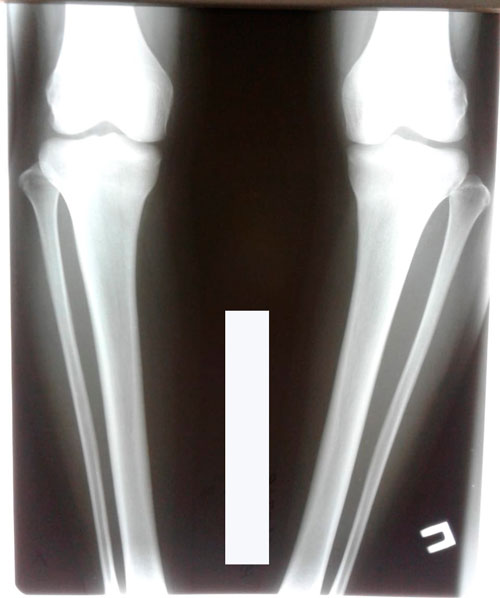

Ножки на сегодня

Дата операции - 13.07.2018г.

Дата снятия аппаратов - 15.10.2018г.

Срок лечения - 90 дней.